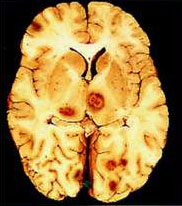

先天性弓形蟲病病變組織診斷檢查

多數是無症狀的帶蟲者,僅少數人發病。臨床表現複雜。先天性弓形蟲病在妊娠期可表現為早產、流產或死產。出生後,可出現各種先天性畸形,包括小腦畸形、腦積水、脊椎裂、無眼、小眼、齶裂等。也可表現為經典的四聯症,即脈絡膜視網膜炎、因大腦發育不良所致精神運動障礙,腦鈣化灶和腦積水。眼部病變除脈絡膜視網膜炎外還可表現為眼肌麻痹、虹膜睫狀體炎、白內障、視神經炎、視神經萎縮和眼組織缺損等。先天性弓形蟲病還可有發熱、多形性皮疹,肺炎、肝脾腫大、黃疸和消化道症狀等臨床表現。